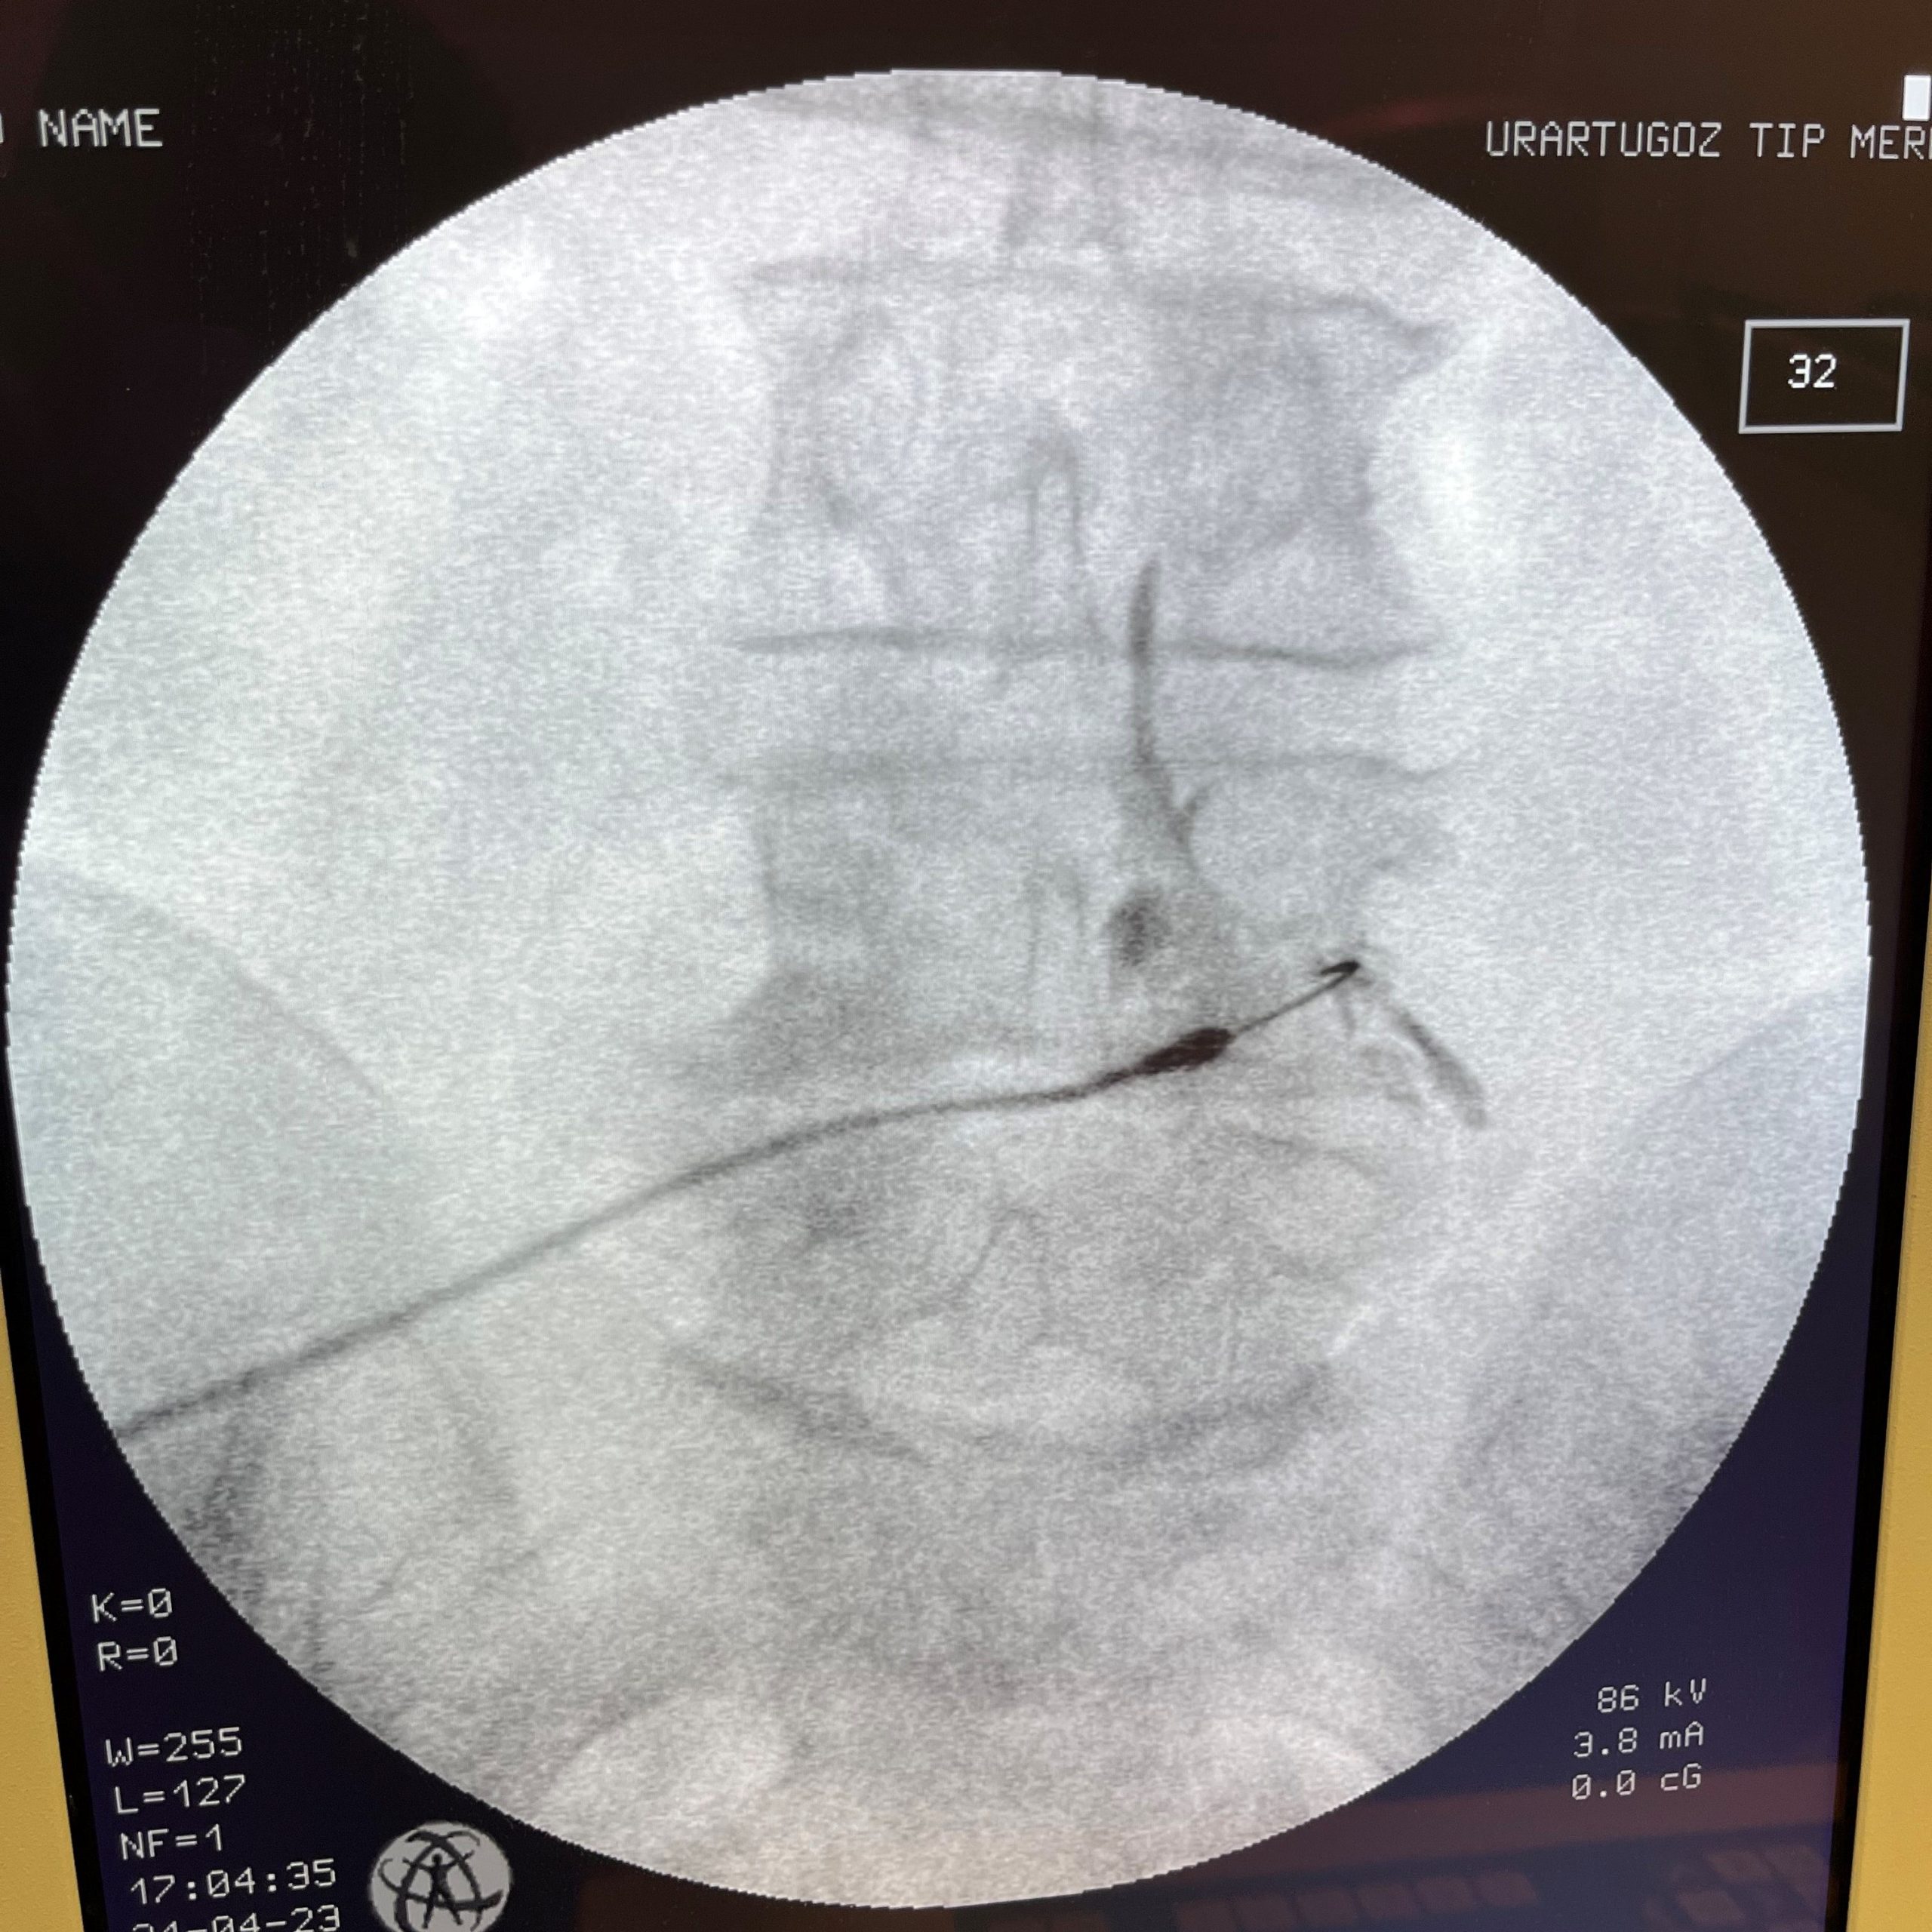

Nokta atışı tedavisinde işlem tam olarak bu fıtık ile sinir kanalına yapılmaktadır.

İşlen uzman hekim tarafından ameliyathanede yapılır. İşlem sırasında iğne ucunu kanala tam olarak yerleştirmek için skopi cihazı kullanılır. Hasta uyutulmaz, işlem sırasında ağrısız bir şekilde işlemi izleyebilir. İşlem ortalama 10 -15 dk sürer.

İşlem ameliyathanede yapılır. Hasa uyutulmaz ancak bazen hafif yatıştırıcı verilebilir. İşlem sırasında fıtığın içerisinde olup olmadığını anlamak için skopi cihazı kullanılır.  İğnenin diskin içerisinde olduğu teyit edildikten sonra uygun dozda ve uygun miktarda ozon gazı disk içerisine verilir.